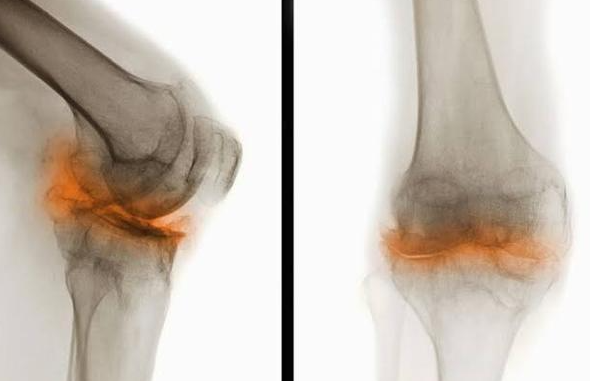

- Osteoarthritis: This is the “wear-and-tear” arthritis many of us have heard about. The smooth cartilage cushion continues to thin and erode. In advanced stages, it can wear away completely, leading to a “bone-on-bone” grinding sensation. The sound you’re hearing is the rough, irregular surfaces of the bones rubbing against each other without their protective cushion.